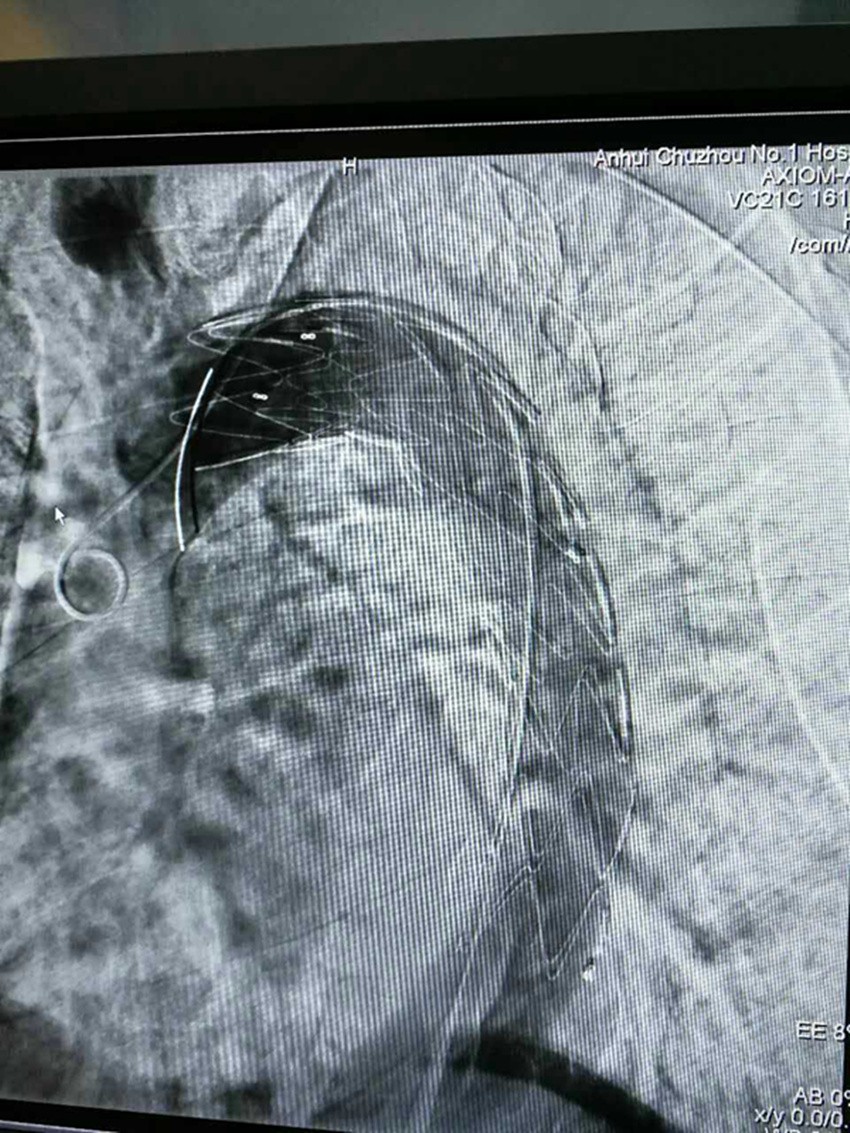

7月15日上午9时,由普外二科汪志刚医师、张文俊主任手术,陆信武教授现场指导,为患者施行局麻,在DSA引导下行经右股动脉穿刺主动脉造影术+主动脉夹层腔内修复术,9:50手术顺利完成。目前病人一切正常,生命体征平稳。

成功植入大血管支架